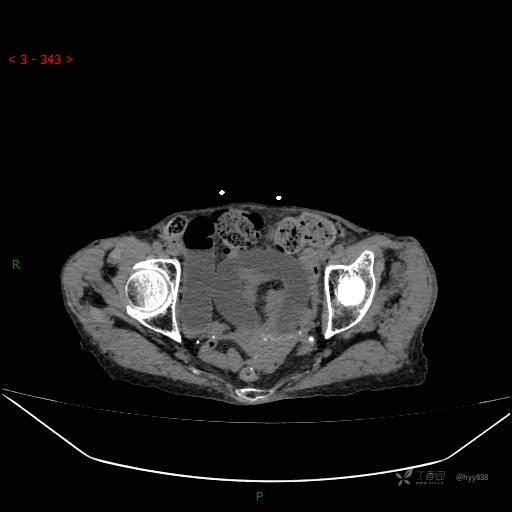

腹部CT平扫